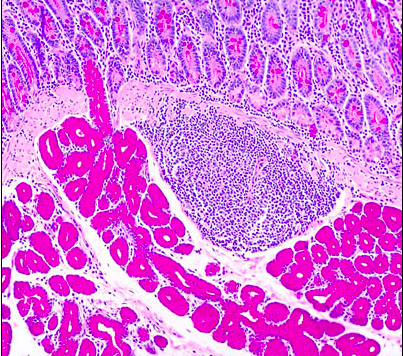

label A-H of the lymph node

A = afferent lymphatic, B =subcapsular sinus, C = cortex, D = medullary cords, E = medulla, F = efferent lymphatic, G = hilus, H = secondary follicles